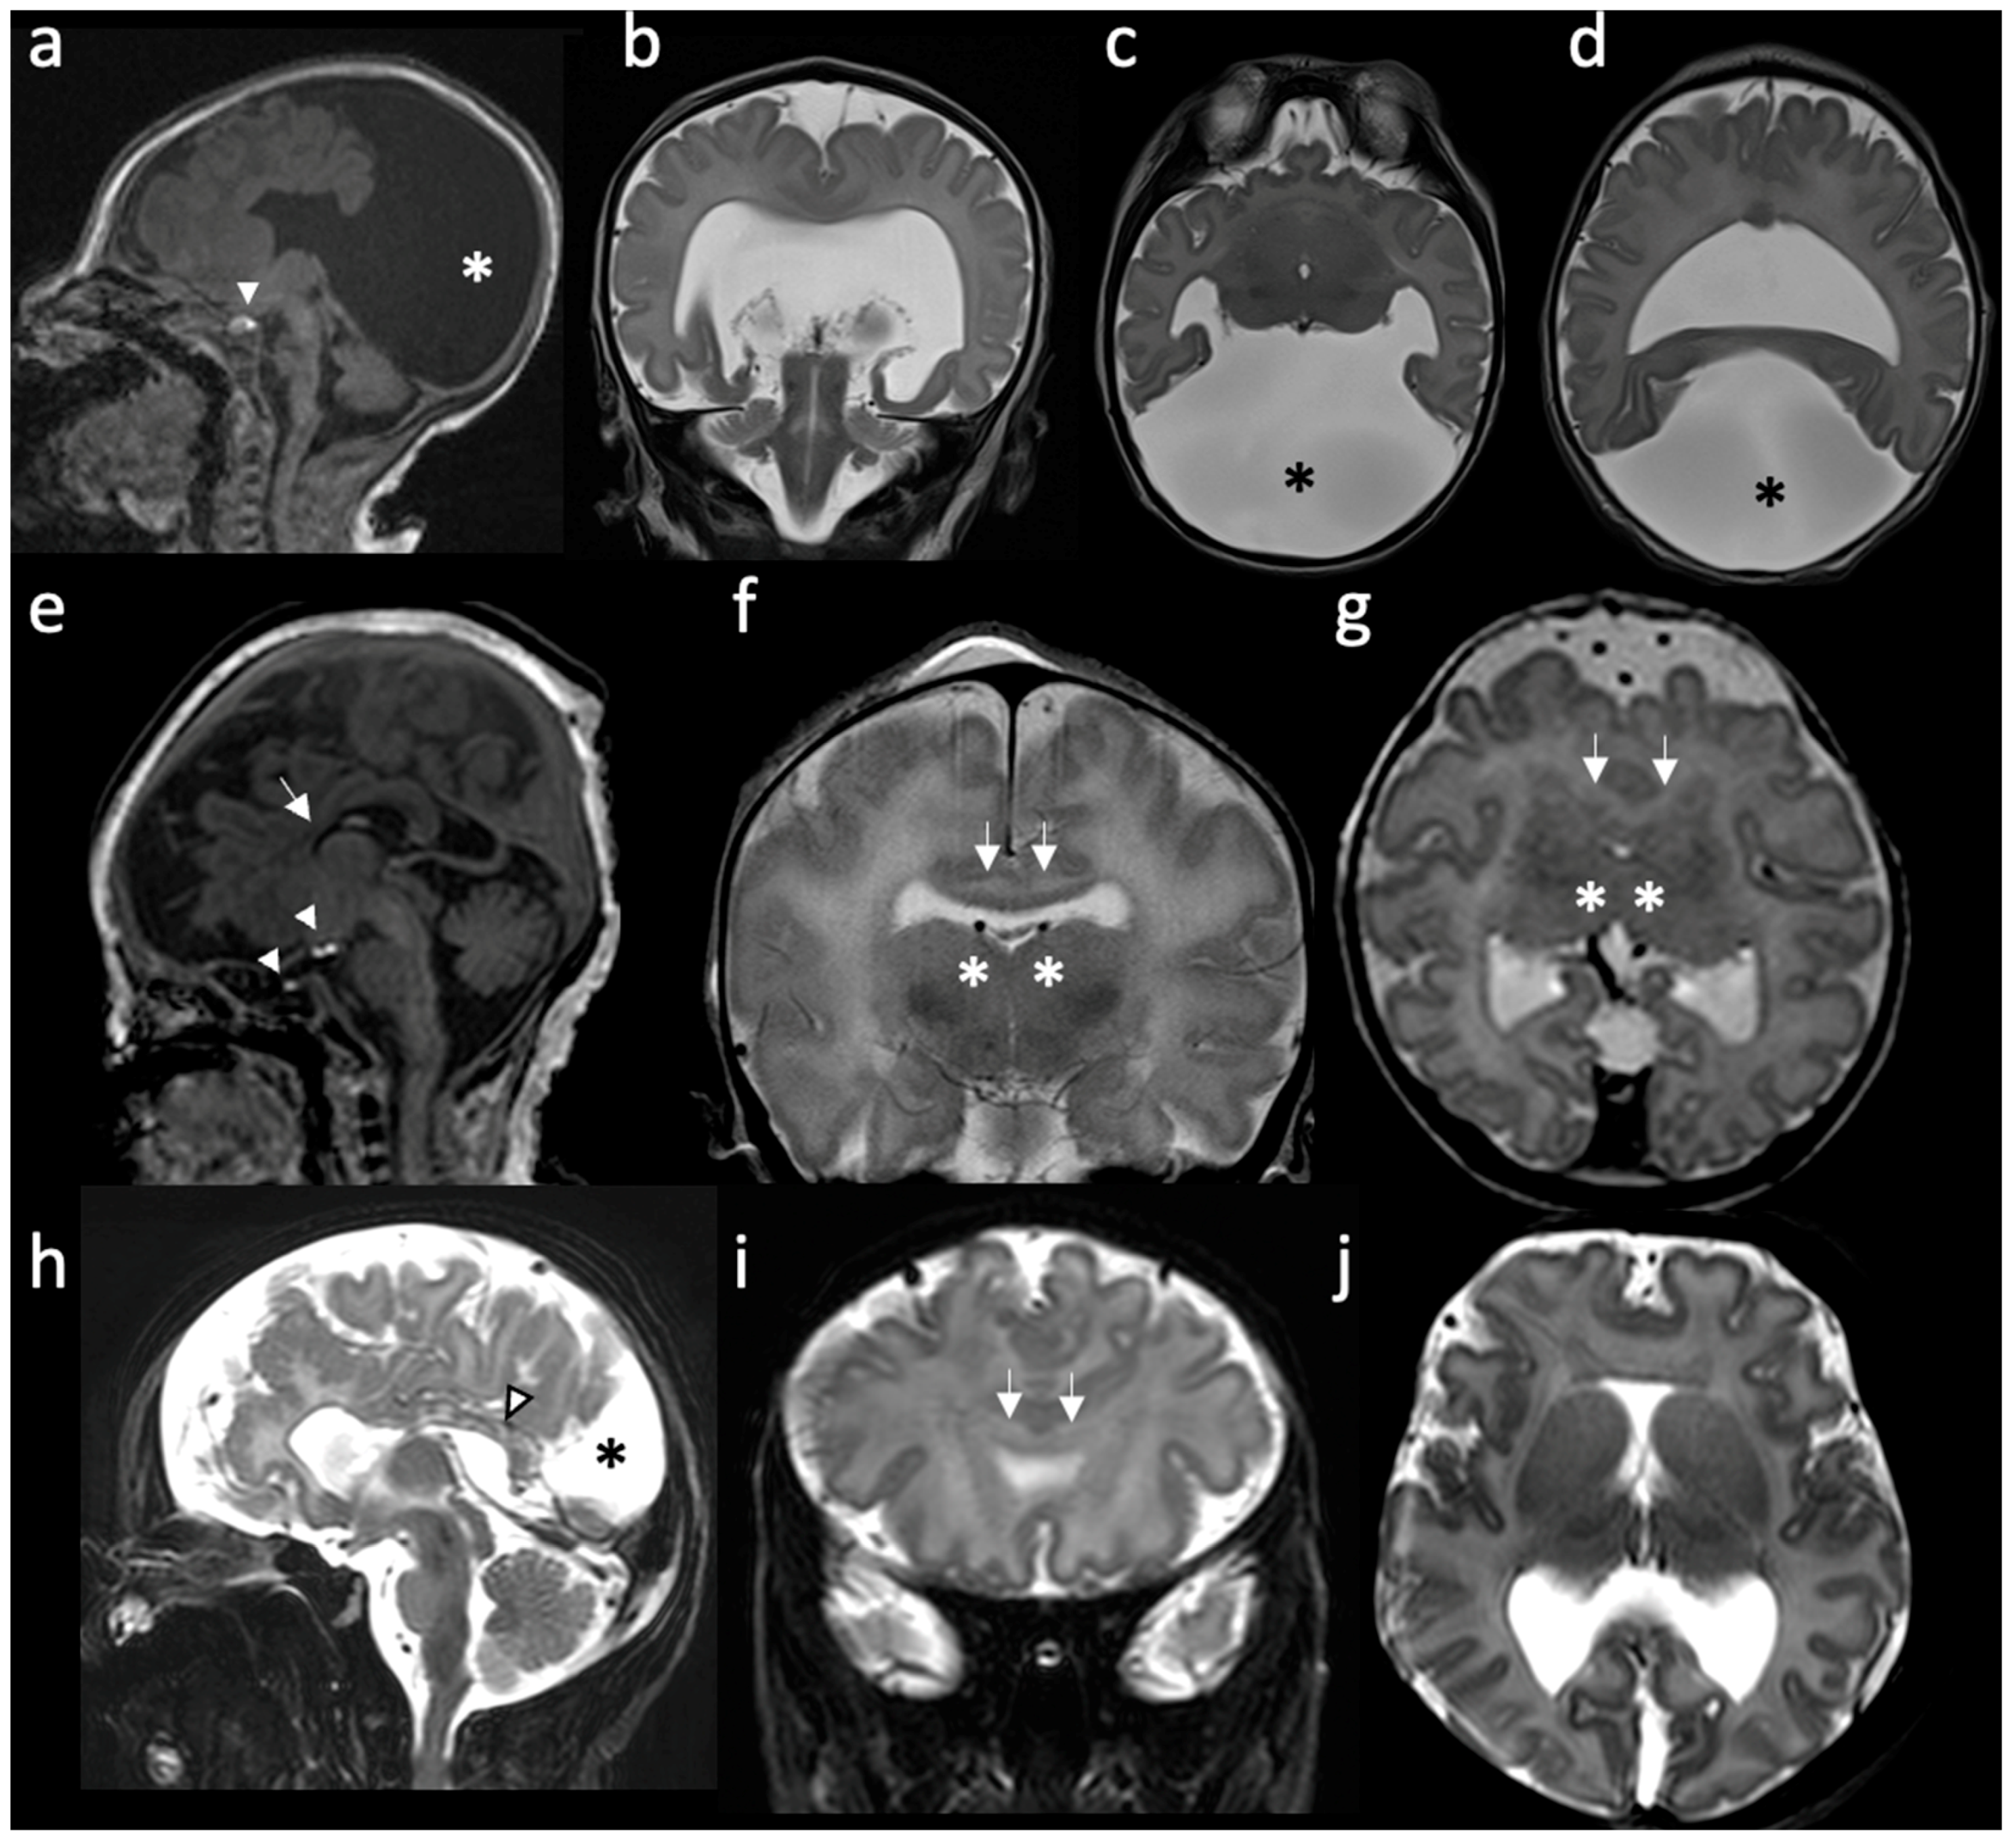

| Type | Main Features | References |

|---|---|---|

| Alobar | Absent separation of the cerebral hemispheres; Single “monoventricle”; Agenesis of the corpus callosum, absent third ventricle; Fusion of thalami and basal ganglia; Dorsal cyst is frequent; Significant midline facial defects. | [6,14,16,19,20] |

| Semilobar | Anterior lobes fail to separate; Interhemispheric fissure detected only posteriorly; Small, partially-formed third ventricle is often noted; Dorsal cyst may also be present; Midline craniofacial defects may be present or only subtle facial abnormalities. | [6,16] |

| Lobar | Only the most rostral-inferior parts of the frontal lobes are fused; Septum pellucidum is usually absent; Posterior half of the corpus callosum is formed; Varying degrees of basal ganglia and thalamic fusion; Midline craniofacial defects often absent or mild. | [6,16,21] |

| Middle interhemispheric variant (syntelencephaly) | Failure of separation of the posterior frontal and parietal lobes; Variable lack of cleavage of the basal ganglia and thalami; Absence of the body but presence of the genu and splenium of the corpus callosum. | [6,16,17,22] |

| Septopreoptic (minimal form) | Midline fusion restricted to the septal region or preoptic region of the telencephalon. | [16] |